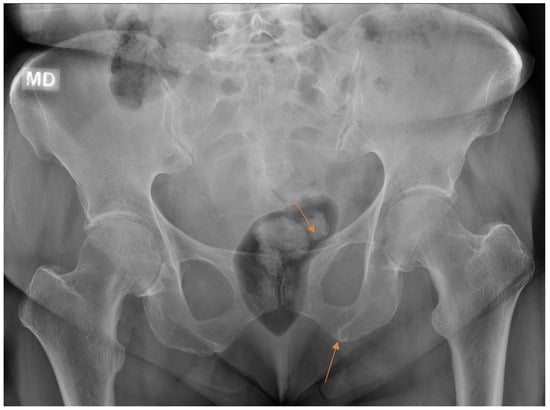

Figure 6.

Patient with pelvic trauma radiographs. Two findings (arrows) initially missed by the resident were later revealed on CT done for other indications.